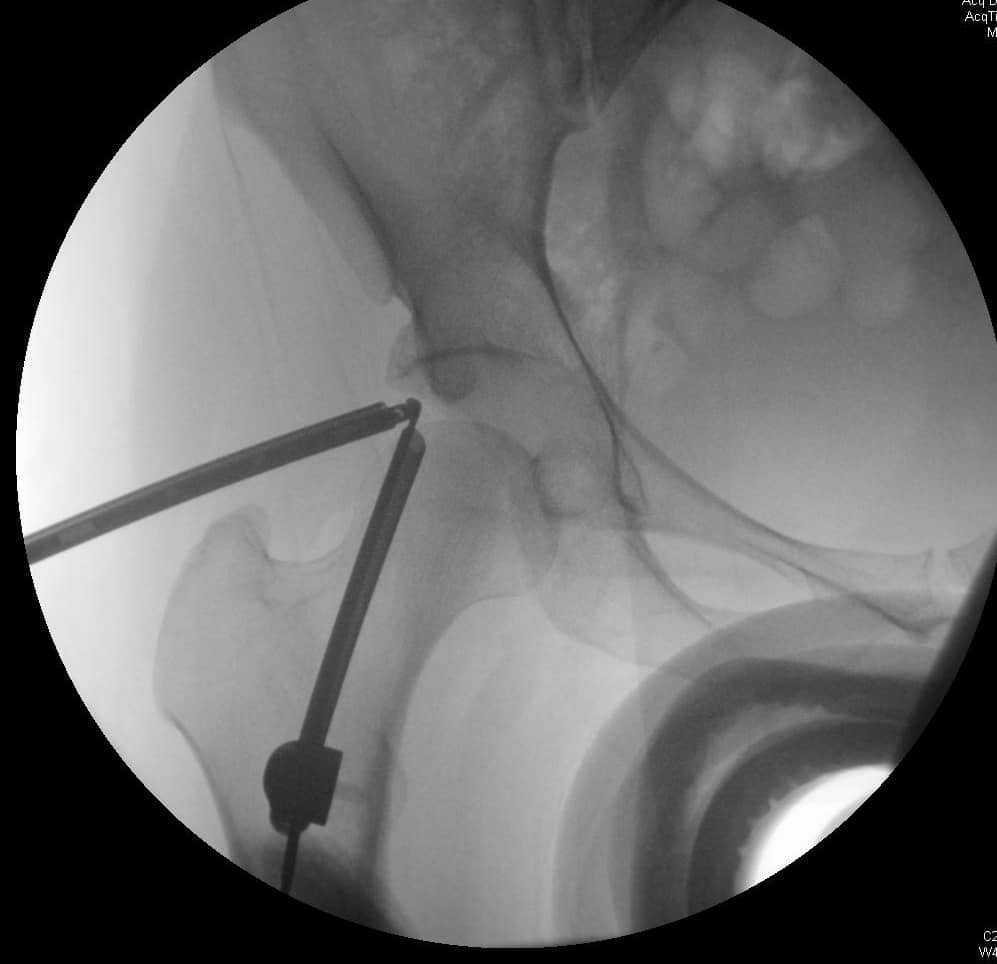

एसिटैबुलर ओस्टियोप्लास्टी और लैब्रल मरम्मत के साथ हिप आर्थ्रोस्कोपी

लैब्रल मरम्मत के साथ या उसके बिना ऊरु गर्दन या एसिटेबुलर ओस्टियोप्लास्टी के साथ हिप आर्थ्रोस्कोपी का उपयोग फेमोरोएस्टेबुलर इम्पैक्टमेंट (एफएआई) के उपचार के लिए किया जा सकता है। रोगी कूल्हे के दर्द और यांत्रिक लक्षणों की घातक शुरुआत के साथ उपस्थित हो सकते हैं और गतिविधि और बैठने के साथ दर्द बदतर हो सकता है। शारीरिक परीक्षा में हिप फ्लेक्सन और आंतरिक रोटेशन कम हो सकता है और पूर्वकाल प्रभाव परीक्षण एफएआई वाले अधिकांश रोगियों में कमर दर्द पैदा करेगा। इमेजिंग कैम-प्रकार या पिंसर-प्रकार के अतिक्रमण के लिए जिम्मेदार घावों को प्रदर्शित कर सकती है, और एमआरआई लैब्रल आंसू या कार्टिलाजिनस घावों का प्रदर्शन कर सकता है। आर्थोस्कोपिक सर्जिकल उपचार उन रोगियों के लिए संकेत दिया जाता है जो रूढ़िवादी उपचार में विफल रहे हैं।

एफएआई के लिए प्रारंभिक गैर-शल्य चिकित्सा प्रबंधन में गतिविधि संशोधन और विरोधी भड़काऊ दवा शामिल है। शल्य चिकित्सा उपचार की प्रगति उन रोगियों के लिए विचार की जानी चाहिए जो रूढ़िवादी प्रबंधन में विफल होते हैं। ऊरु गर्दन के घावों या लैब्रल आंसुओं के सर्जिकल उपचार का इलाज खुले या आर्थोस्कोपिक डिब्राइडेशन और लैब्रल मरम्मत या शोधन द्वारा किया जा सकता है। खुले उपचार के संकेतों में गैर-गोलाकार ऊरु सिर, सिर-गर्दन ऑफसेट में कमी, पिंसर का टकराव, और पीछे के कूल्हे के घाव शामिल हैं। बर्नीज़ पेरियासेटाबुलर ओस्टियोटॉमी एक खुली एसिटेबुलर रीओरिएंटेशन प्रक्रिया है जिसका लक्ष्य एसिटेबुलर रेट्रोवर्जन को कम करना है। एसिटाबुलम की चोंड्रल चोटों का इलाज चोंड्रोप्लास्टी, ड्रिलिंग या माइक्रोफ्रैक्चर द्वारा किया जा सकता है, जिसका उद्देश्य फाइब्रोकार्टिलेज रीग्रोथ को प्रोत्साहित करना है। एसिटेबुलर एंटीवर्सन और पश्चवर्ती ओस्टियोफाइट के प्रभाव का इलाज एसिटाबुलम के रिम एक्सिशन के साथ किया जा सकता है। आर्थोस्कोपिक नैदानिक परिणाम एफएआई के उपचार के लिए खुले सर्जिकल नैदानिक परिणामों के समान दिखाई देते हैं। 2, 3

एफएआई के लिए सर्जिकल मरम्मत पर्याप्त संयुक्त स्थान वापस करने का प्रयास करती है ताकि एसिटाबुलम के खिलाफ ऊरु सिर या गर्दन के झुकाव के बिना कूल्हे की गति की अनुमति मिल सके। इस स्थान को कम करने वाले घावों का छांटना अपक्षयी प्रक्रिया को संभावित रूप से धीमा करने और दर्द और अन्य लक्षणों को हल करने के लिए किया जाता है। आर्थ्रोस्कोपी समान नैदानिक परिणामों के साथ पारंपरिक खुली सर्जरी के लिए एक कम-आक्रामक विकल्प प्रदान करता है। 4, 7